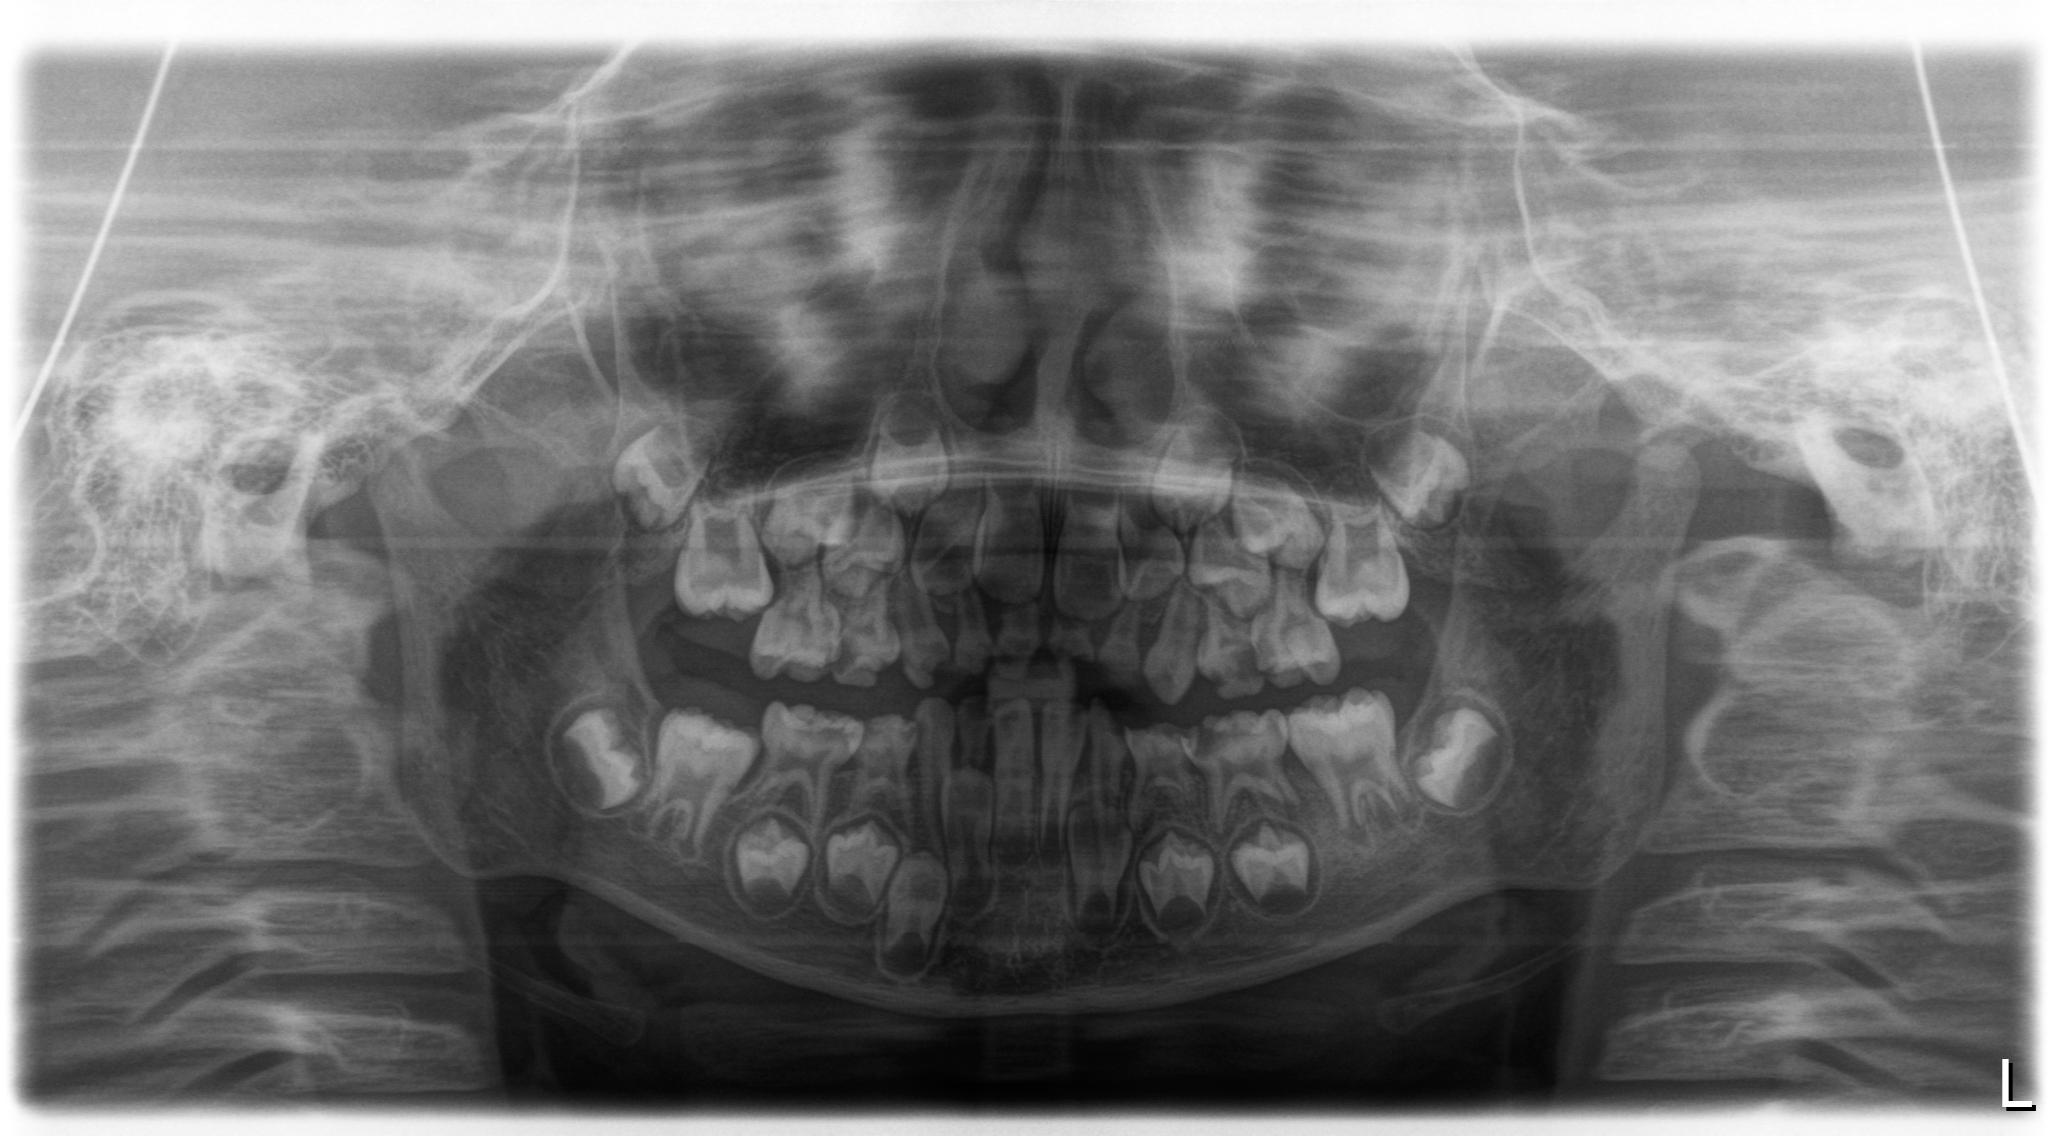

上图示:6岁小孩,该片子示显示见到智齿的影像的。

上图示:10岁的小孩,通过拍片常规检查的时候可以发现图片的左下角有一个暗暗的影像,就是智齿的牙囊,还在刚刚开始发育的智齿,全景片上检查发现仅仅只有一颗智齿生长。其他的都进化消失了。